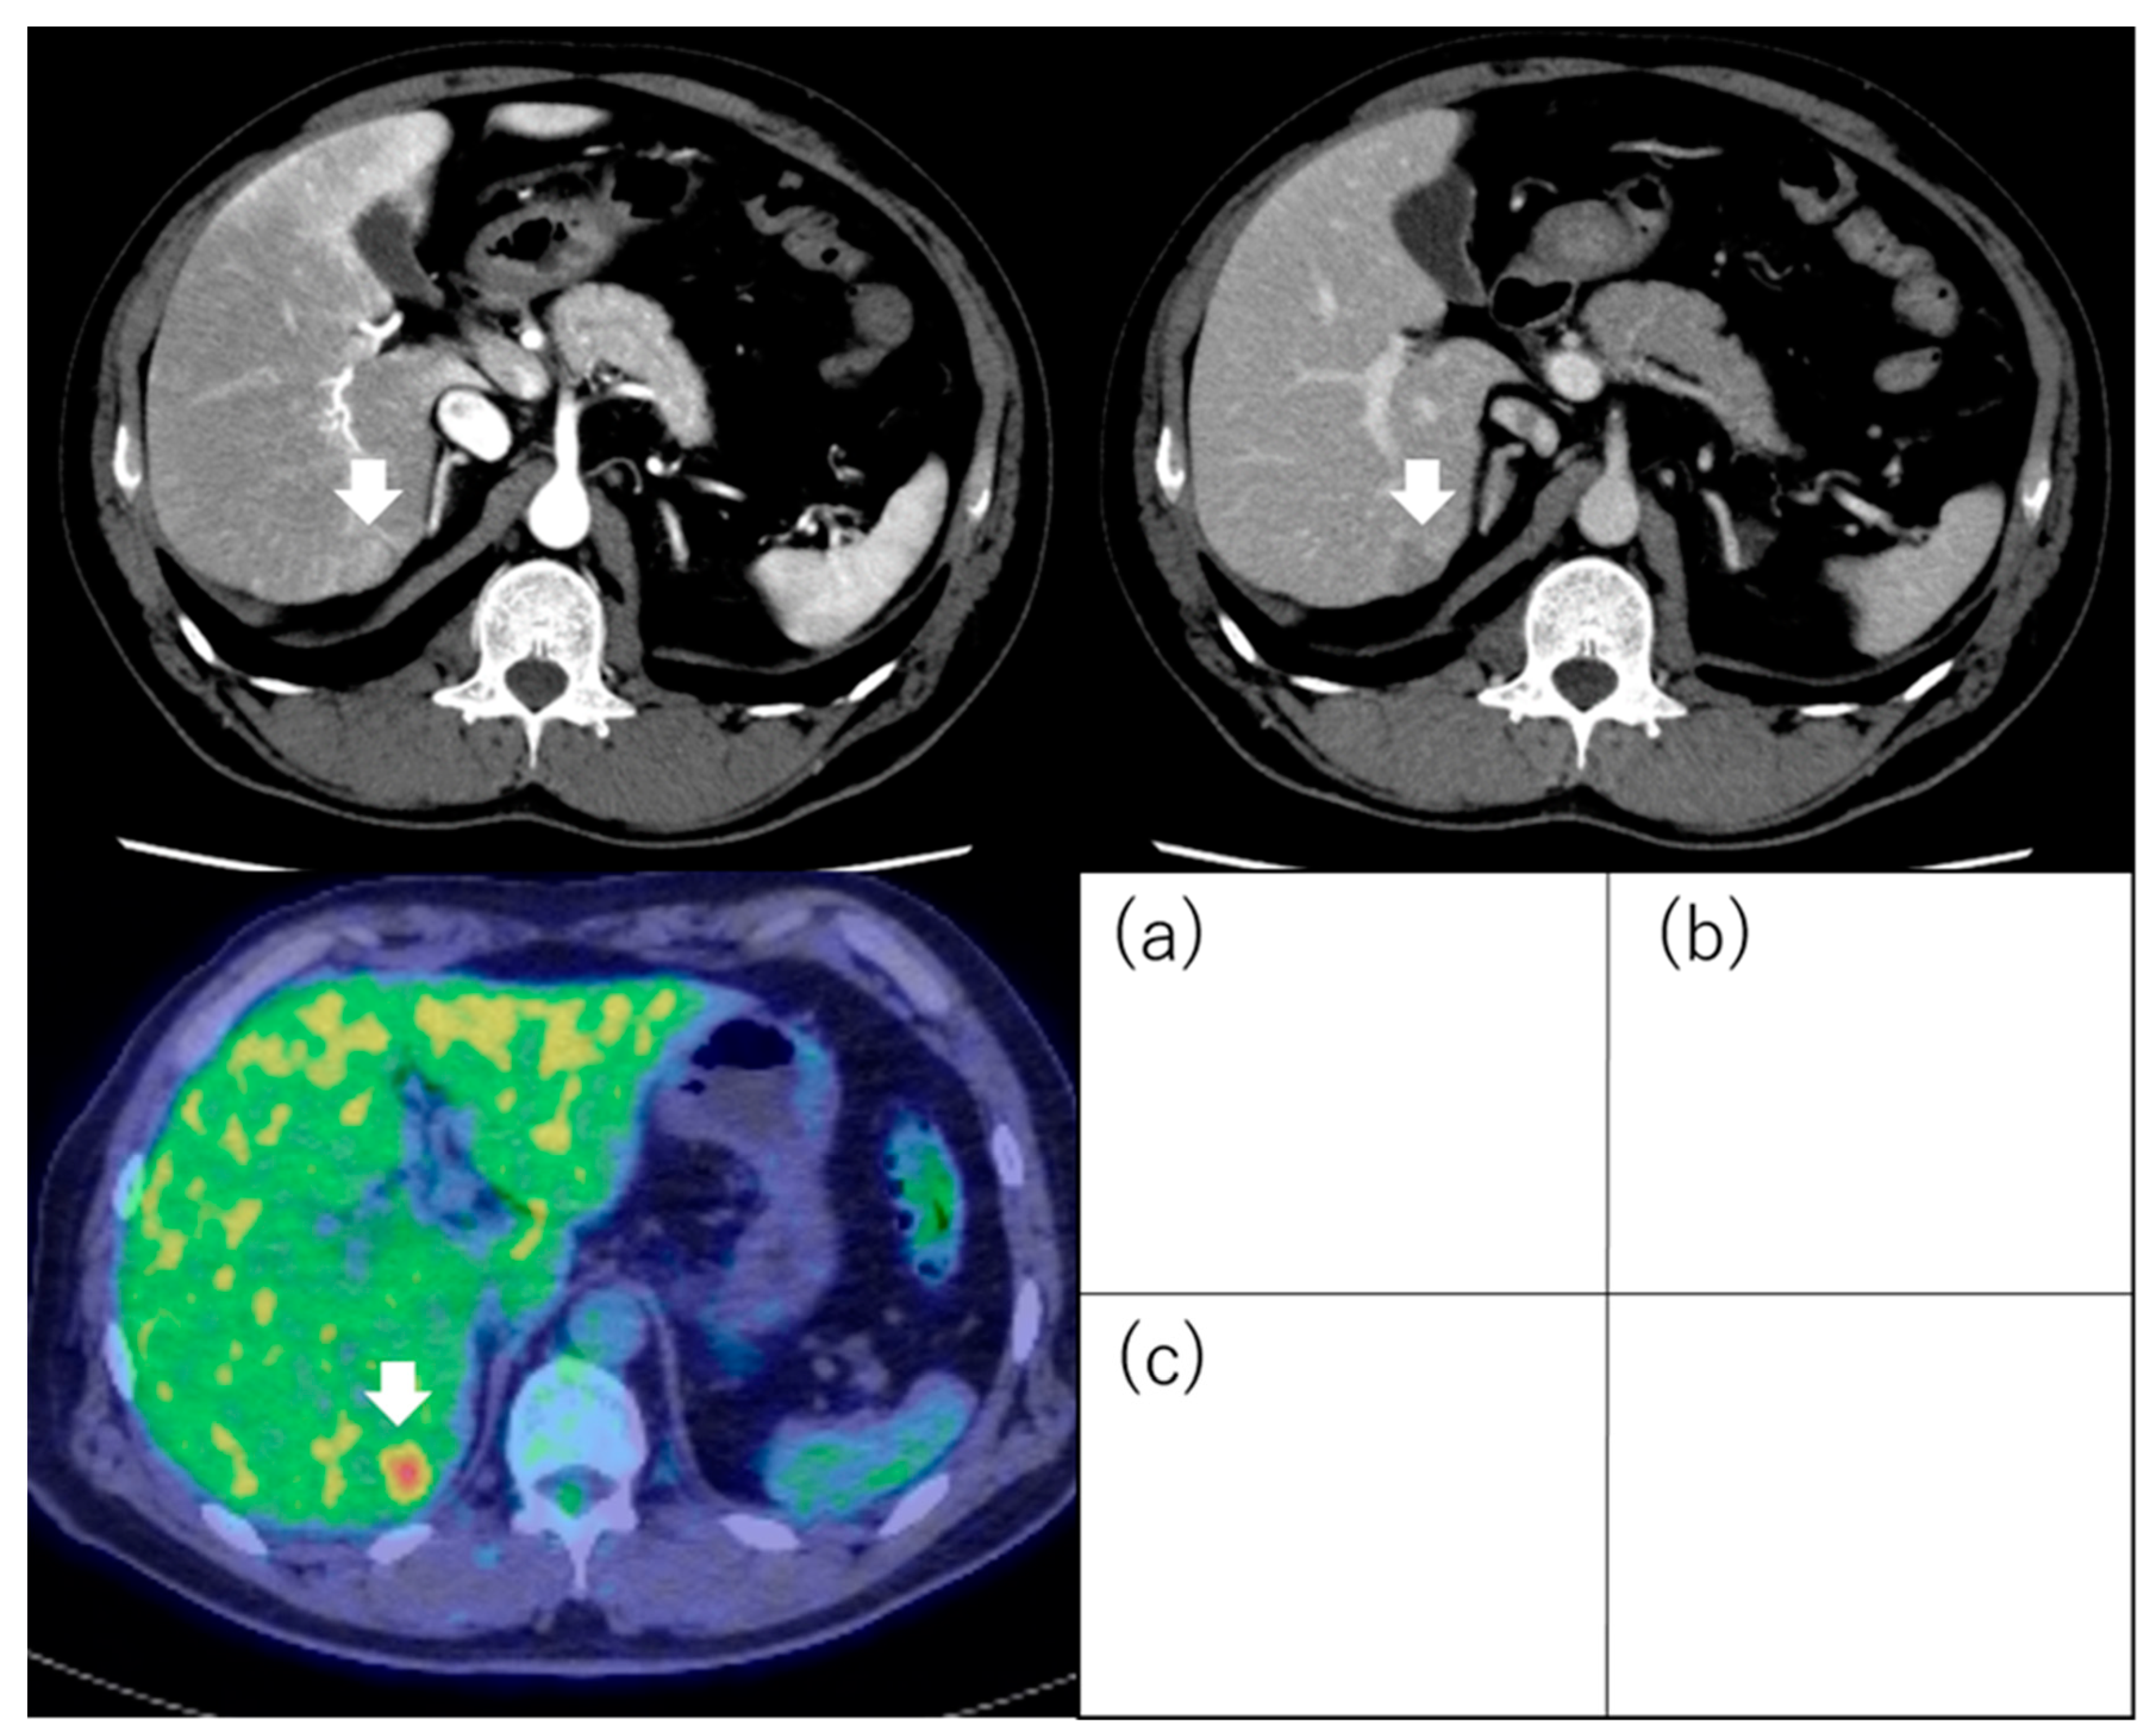

5. 18F-Fluorodeoxyglucose Positron Emission Tomography

5.1. Standardized Uptake Value

5.2. 18F-Fluorodeoxyglucose Uptake

- Hyun, S.H.; Eo, J.S.; Lee, J.W.; Choi, J.Y.; Lee, K.-H.; Na, S.J.; Hong, I.K.; Oh, J.K.; Chung, Y.A.; Song, B.-I.; et al. Prognostic value of 18F-fluorodeoxyglucose positron emission tomography/computed tomography in patients with Barcelona Clinic Liver Cancer stages 0 and A hepatocellular carcinomas: A multicenter retrospective cohort study. Eur. J. Nucl. Med. Mol. Imaging 2016, 43, 1638–1645. [Google Scholar] [CrossRef]

- Cho, K.J.; Choi, N.K.; Shin, M.H.; Chong, A.R. Clinical usefulness of FDG-PET in patients with hepatocellular carcinoma undergoing surgical resection. Ann. Hepato-Biliary-Pancreat. Surg. 2017, 21, 194–198. [Google Scholar] [CrossRef]

- Hyun, S.H.; Eo, J.S.; Song, B.I.; Lee, J.W.; Na, S.J.; Hong, I.K.; Oh, J.K.; Chung, Y.A.; Kim, T.S.; Yun, M. Preoperative prediction of microvascular invasion of hepatocellular carcinoma using (18)F-FDG PET/CT: A multicenter retrospective cohort study. Eur. J. Nucl. Med. Mol. Imaging 2018, 45, 720–726. [Google Scholar] [CrossRef] [PubMed]

- Yoh, T.; Seo, S.; Ogiso, S.; Kawai, T.; Okuda, Y.; Ishii, T.; Taura, K.; Higashi, T.; Nakamoto, Y.; Hatano, E.; et al. Proposal of a New Preoperative Prognostic Model for Solitary Hepatocellular Carcinoma Incorporating 18F-FDG-PET Imaging with the ALBI Grade. Ann. Surg. Oncol. 2018, 25, 542–549. [Google Scholar] [CrossRef] [PubMed]

- Keyes, J.W., Jr. SUV: Standard uptake or silly useless value? J. Nucl. Med. Off. Publ. Soc. Nucl. Med. 1995, 36, 1836–1839. [Google Scholar]

- Hernandez-Martinez, A.; Marin-Oyaga, V.A.; Salavati, A.; Saboury, B.; Codreanu, I.; Lam, M.G.E.H.; Torigian, D.A.; Alavi, A. Quantitative assessment of global hepatic glycolysis in patients with cirrhosis and normal controls using 18F-FDG-PET/CT: A pilot study. Ann. Nucl. Med. 2014, 28, 53–59. [Google Scholar] [CrossRef] [PubMed]

- Ida, Y.; Tamai, H.; Shingaki, N.; Shimizu, R.; Maeshima, S.; Maekita, T.; Iguchi, M.; Terada, M.; Kitano, M. Prognostic value of (18)F-fluorodeoxyglucose positron emission tomography in patients with small hepatocellular carcinoma treated by radiofrequency ablation. Cancer Imaging Off. Publ. Int. Cancer Imaging Soc. 2020, 20, 74. [Google Scholar] [CrossRef]

| Hyun et al. [79] | 317 | BCLC stage 0 or A | Curative treatment (LR or RFA or LTP) (195) TACE (122) | TLR (cutoff value; 2.0) | Outcome (recurrence, OS) | TLR ≥ 2.0 was an independent factor for OS in curative treatment group (HR, 2.68; 95% CI, 1.16–6.15; p = 0.020). |

| Hyun et al. [81] | 158 | BCLC stage 0 or A | LR | TLR (cutoff value; 1.3) | Microvascular invasion Outcome (recurrence) | Predictability of TLR for microvascular invasion as follows: sensitivity was 85.5%, specificity was 54.9%, positive predictive value was 63.7%, negative predictive value was 80.4%. TLR was one of the independent factors for metastatic recurrence (HR, 2.43; 95% CI, 1.01–5.84; p = 0.047). |

| Yoh et al. [82] | 207 | Solitary | LR | TNR (cutoff value; 2.0) | Outcome (recurrence, OS) | TNR was one of the independent factors for OS (HR, 1.743; 95% CI, 1.114–2.648; p = 0.016). |

| Ida et al. [85] | 121 | ≤3 tumors and ≤3 cm | RFA | Outcome (recurrence, OS) | PET positivity was one of the independent factors for metastatic recurrence (HR, 10.297; 95% CI, 3.128–33.898; p < 0.001) and OS (HR, 7.300; 95% CI, 1.920–27.751; p = 0.004). |